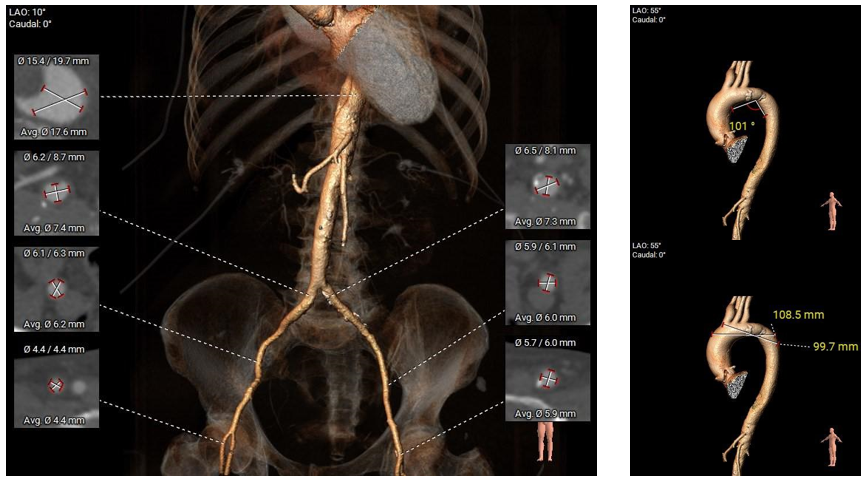

病例二 患者基本信息

男性,84岁。间断胸闷20余年,加重7月,再发10天,夜间不能平卧,双下肢中重度凹陷性水肿。超声心动图提示:主动脉瓣峰值流速5.3m/s,峰值压差114mmHg,瓣口面积0.5cm²,EF值34%。主动脉瓣重度狭窄并少量反流,二尖瓣中量反流,三尖瓣大量反流;全心增大,升主动脉宽,肺动脉高压。

主动脉根部评估

根部概览

钙化概览

三叶瓣,窦部空间可,心室明显扩大。

多平面分析

敞口状流出道,瓣上限制较重,瓣膜释放后存在一定下滑风险。

冠脉分析

冠脉开口高度可,未见冗长瓣叶,预估冠脉遮挡风险较低。

外周分析

外周概览(钙化)

外周概览

入路血管走形良好,无明显附壁钙化,弓部条件良好,预估过弓、跨瓣顺利。

手术策略及难点分析

• 三叶瓣,瓣叶中重度钙化,瓣膜锚定力可,瓣上限制较重,预估瓣膜释放后存在一定下滑风险;

• EF值34%,心腔增大,心功能较差,术中潜在循环崩溃及心室损伤风险;

• 预计采用22mm球囊预扩,植入TaurusElite AV26瓣膜,工作位充分评估瓣膜位置、形态、冠脉灌注及瓣周漏情况,确认无误再行释放,ECMO备台。